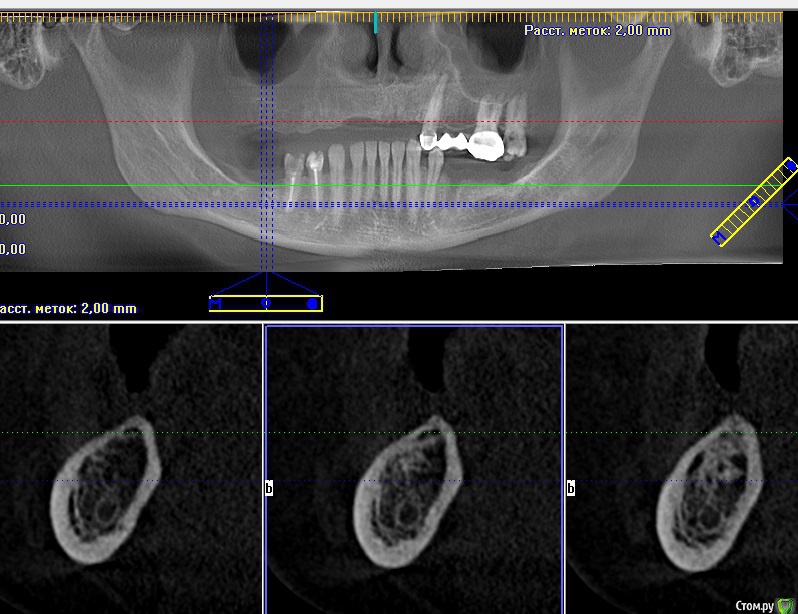

kriokov Опубликовано 16 июля, 2016 Поделиться Опубликовано 16 июля, 2016 Найду залью скрины кт до и прицельный снимок после фиаско 3 Ссылка на комментарий

kamranchick Опубликовано 18 июля, 2016 Автор Поделиться Опубликовано 18 июля, 2016 Снимок экрана (7).jpgав.jpgВ итоге что сделали? Ссылка на комментарий